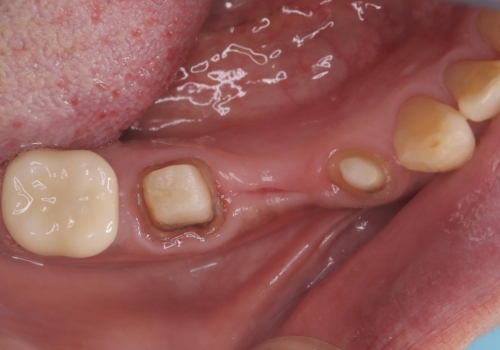

コアごと脱離して来院し、フェルールの獲得が厳しいためコアが立てられないので抜歯することになりました。

インプラントとブリッジの治療を提案し早く噛めるようにしてほしいという要望があったためブリッジにて治療をすることになりました。